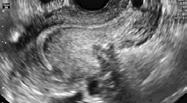

Diagnosticul este evaluat prin ecografia transvaginală (ETV) și stabilit prin

biopsia de endometru, prelevată prin histeroscopie, aspirație endometrială sau curetaj clasic (4)

Ecografia transvaginală este un instrument esențial, de prima linie, în diagnosticul CE. Dacă grosimea endometrului este ≤ 5 mm, biopsia endometrială nu este necesară. Dacă totuși sângerarea persistă, este necesară o histeroscopie cu repetarea examenului HP.

Alteori ETV evidențiază o colecție lichidiană endocavitară asociată cu o proeminență endocavitară, sau chiar o formațiune tumorală. Tot ETV permite și evaluarea invaziei miometriale.